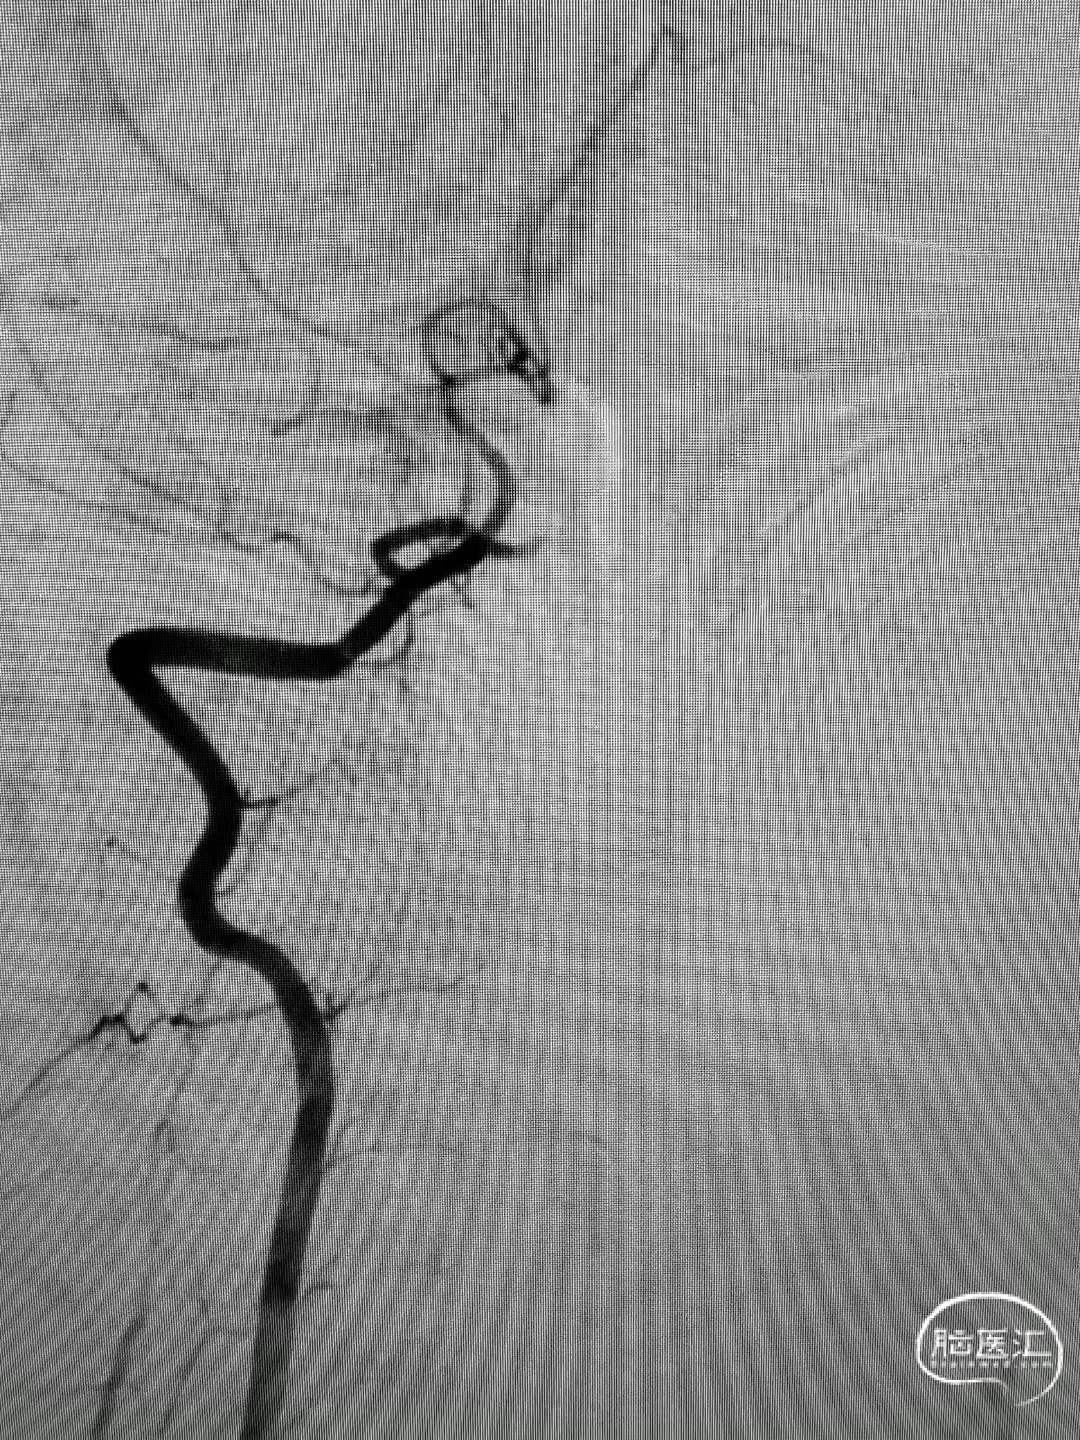

造影见基底动脉闭塞。

a4ca8e833a2e8a51bafe6033253675cc.jpg